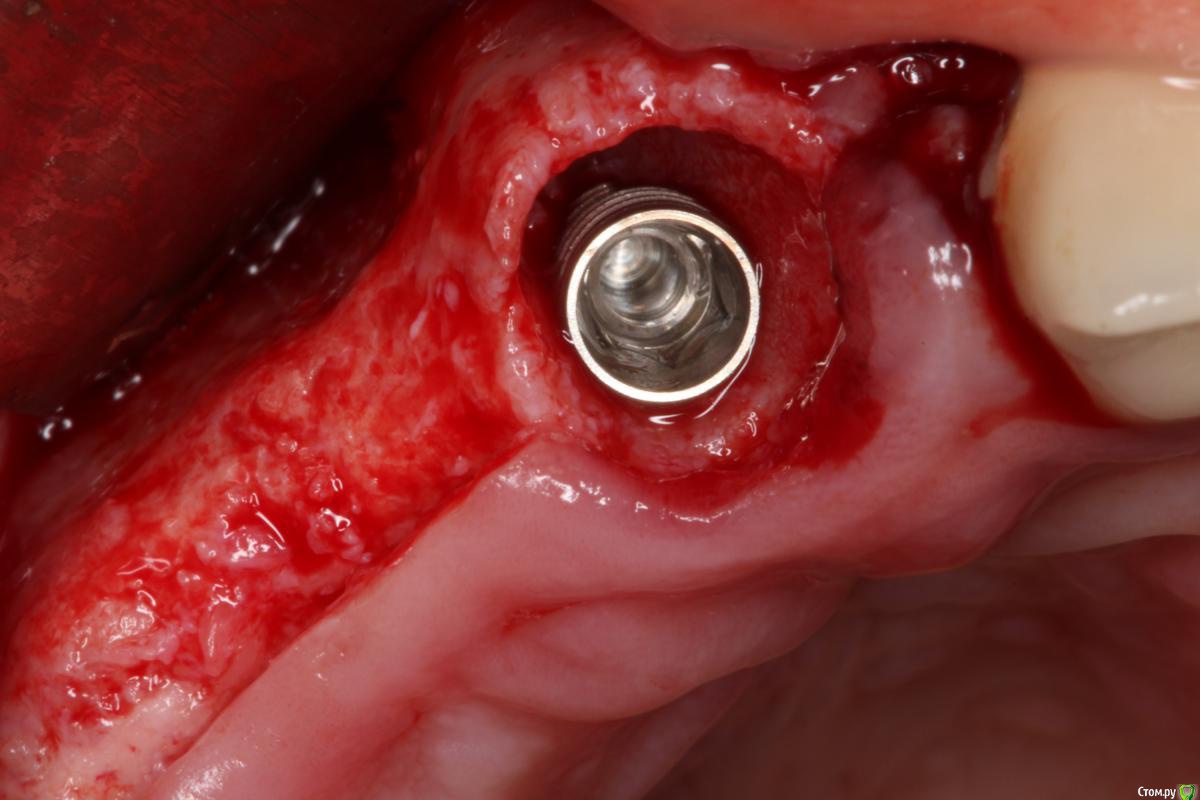

Robinbobin Опубликовано 9 сентября, 2015 Поделиться Опубликовано 9 сентября, 2015 Зуб 1.1 удалил,кюретаж и одномоментно установлен имплантат, заполнил MP3 и закрутил заглушкуУстановил имплантаты в области 1.3,1.4 подсыпал так же MP3 под мембрану и запинилЕсли покажите пальцем на ошибки буду благодарен))) 4 Ссылка на комментарий

Большой Зеленый Опубликовано 9 сентября, 2015 Поделиться Опубликовано 9 сентября, 2015 11 имплант нужно было медиальнее ставить и чуть еще утопить платформу 1 Ссылка на комментарий

колесников Опубликовано 9 сентября, 2015 Поделиться Опубликовано 9 сентября, 2015 Одномоментно желательно глубже ставить ,до 2мм по гребню уходит в последствии. У 12 обязательно сст . Впрочем можно было и в обл 13,14 им обойтись,но это дело вкуса. П-образный шов препочтителен,не будет расхождений и дополнительный объем на вершине получается. Ссылка на комментарий

Bier Опубликовано 13 сентября, 2015 Поделиться Опубликовано 13 сентября, 2015 ставить нужно учитывая шейку будущего зуба, а не глубже "потому что часть кости уйдет" Тут будет некрасивая ортопедия. 2 Ссылка на комментарий

SergeyAL Опубликовано 13 сентября, 2015 Поделиться Опубликовано 13 сентября, 2015 полностью согласен, у ортопеда будет много проблем с эстетикой из-за разного уровня шеек имплантатов. Ссылка на комментарий